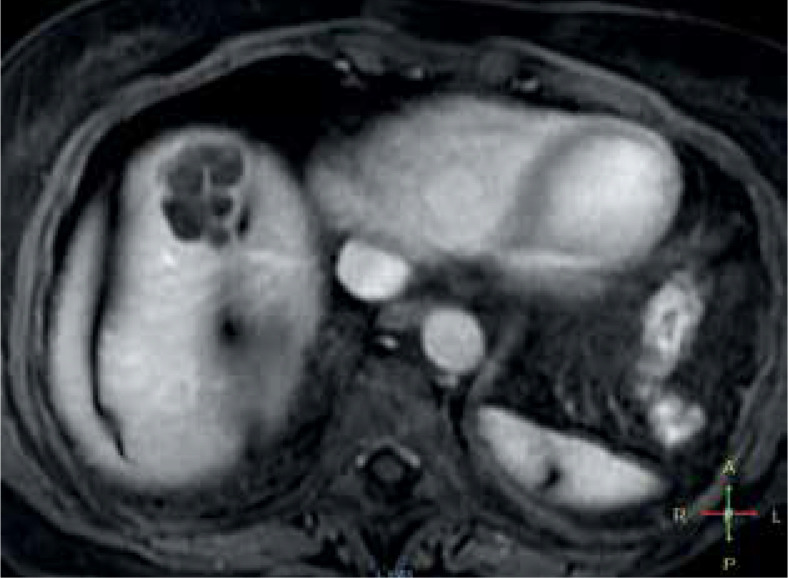

Echinococcosis is considered one of the world's most dangerous zoonoses, and the tapeworm that causes it is one of the two most dangerous parasites to humans globally. Untreated cases may be associated with as high as 90% mortality. The incidence of this pathology is increasing. The authors present an up-to-date review of the literature on liver echinococcosis; they also present their own material of 73 patients with liver echinococcosis treated in the Department of General and Transplant Surgery since 2019.